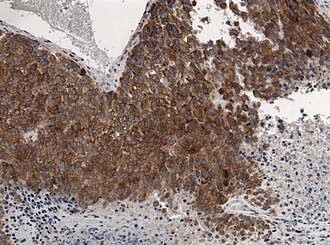

BRAF V600E positivity in malignant melanoma. VE1 immunostain.

The mutation can be demonstrated with molecular testing (ARMS). Also, a mutation specific immunostain (VE1) is available.[1]